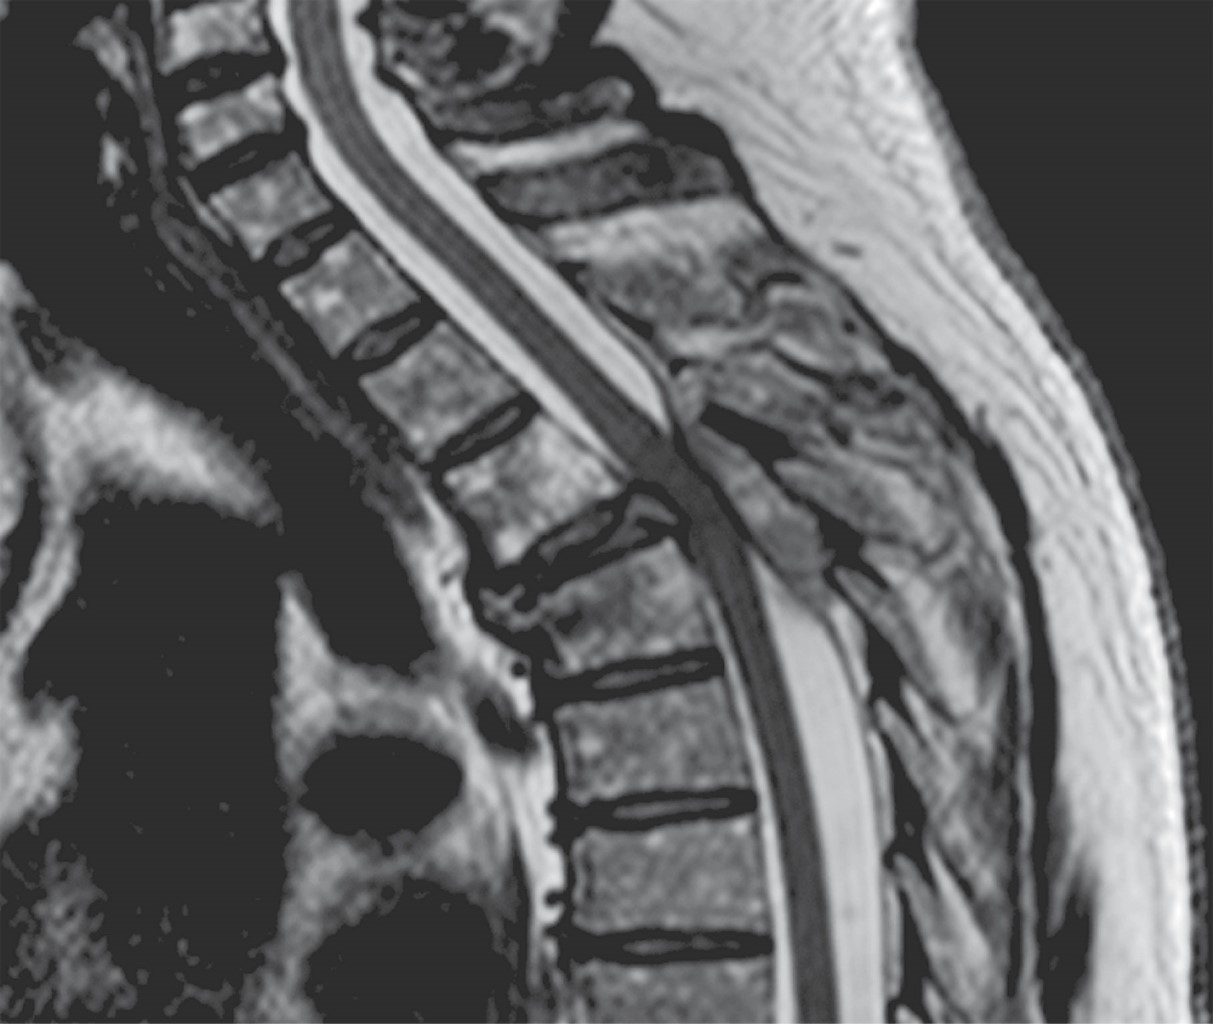

A la exploración neurológica con fuerza 1/5 en miembros inferiores se observa hipotonía, reflejos de estiramiento muscular de miembros inferiores 1/4, con hipoestesia por debajo de T4. Se realizó resonancia magnética en vista sagital secuencia T2, donde se aprecia lesión hipointensa epidural localizada en T4-T5 de bordes regulares con dimensiones de 35 × 6 mm que, de acuerdo con la clasificación de SINS, obtuvo puntaje de 4, catalogándose como columna inestable. Por lo anterior se decidió realizar cirugía, la cual consistió en hemilaminectomía de T4-T5 más exéresis tumoral, reportándose en el examen de patología transquirúrgico como plasmocitoma (Figuras 1, 2 y 3).

A diferencia de lo que proponen algunos algoritmos de manejo conservador inicial sólo con radioterapia, en este caso se optó por intervención quirúrgica temprana con biopsia escisional como estrategia diagnóstica y terapéutica simultánea. Esta decisión, fundamentada en la presencia de déficit neurológico progresivo y compresión medular evidente en la resonancia magnética, permitió una descompresión efectiva y un rápido control local de la enfermedad.